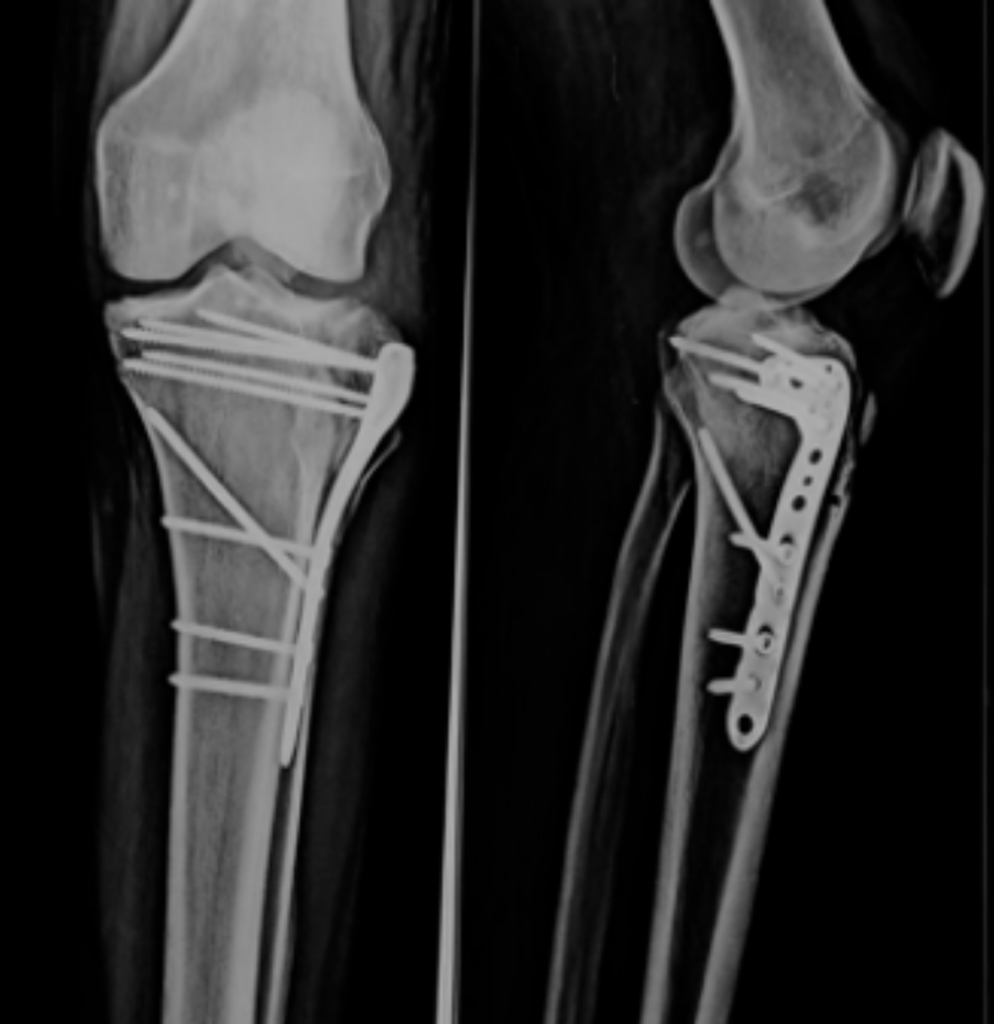

While both FRIs and PJIs involve biofilm formation, FRIs are complicated by factors like the presence of a fracture, ongoing bone healing, and soft tissue injuries. These elements make treatment more complex than in PJIs.

In PJIs, the primary goal is to eradicate infection, often requiring implant removal. However, in FRIs, the focus is on fracture healing and preventing chronic osteomyelitis. In some cases, complete infection eradication may not be immediately necessary, and suppressive antibiotics can serve as a temporary measure until implant removal is viable.